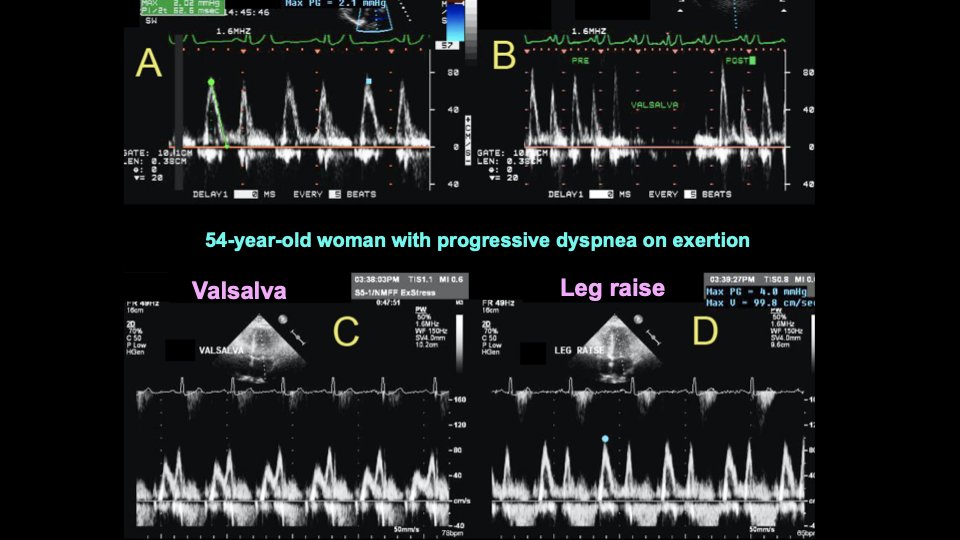

Effect of passive leg raise on mitral inflow is also helpful. In the example 👇, A=rest, B=after release of Valsalva maneuver (Valsalva done incorrectly). C=correct Valsalva showing E/A reversal (=DD is grade 2). D=⬆️⬆️E velocity to 100 cm/s with leg raise (from 70 cm/s at rest).